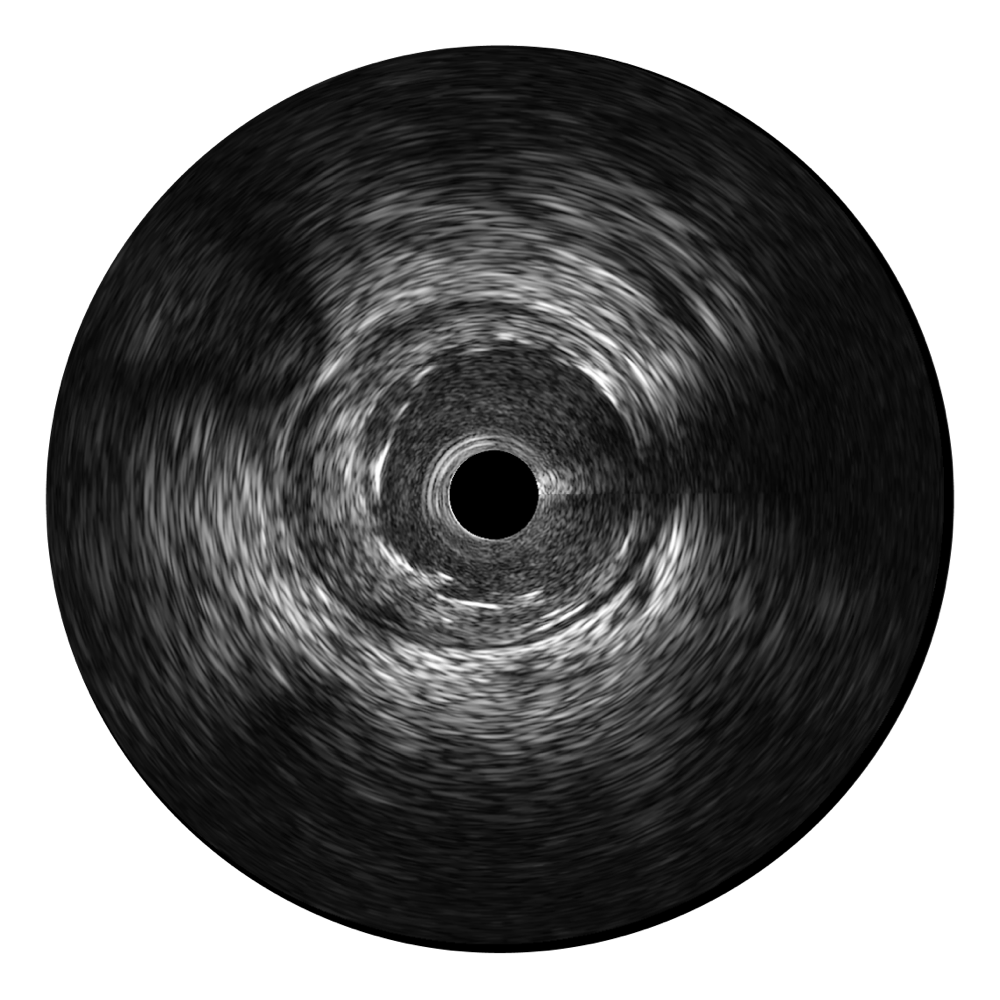

• 银河优越会宽频IVUS图像

对比传统IVUS导管成像,银河优越会宽频IVUS图像的近场支架梁显影更细腻,远场中膜外血管仍清晰可辨,兼顾远中近,兼顾分辨力与穿透深度